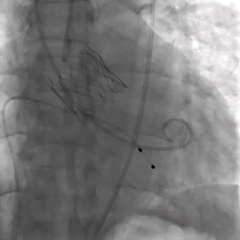

无窦侧0位起始,最终释放深度满意

多角度评估位置合适,无瓣周漏

瓣膜释放后无位移,锚定牢固

术后超声可见反流消失,血流动力学正常